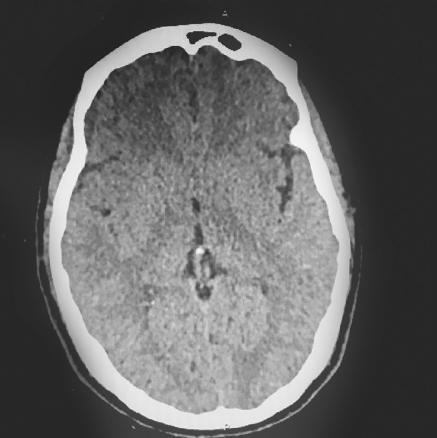

Cette femme de 38 ans consultait pour des céphalées en casque évoluant depuis une semaine. La patiente précisait avoir une rhinorrhée antérieure depuis une intervention neurochirurgicale sur adénome hypophysaire réalisée un mois auparavant. L’examen ne notait ni atteinte des paires crâniennes ni céphalée orthostatique. La patiente était apyrétique et son bilan biologique ne montrait pas de syndrome inflammatoire ou infectieux. Une liquorrhée cérébrospinale était visualisée au contact du sphénoïde à la rhinoscopie. La tomodensitométrie cérébrale était normale (fig. 1 ). La patiente était hospitalisée et, le soir même, chutait dans la salle de bains. Une nouvelle tomodensitométrie (48 h après la première) montrait une pneumencéphalie diffuse témoignant d’une brèche méningée (fig. 2 ). La chute a probablement accentué la brèche, occasionnant la pneumencéphalie secondaire.